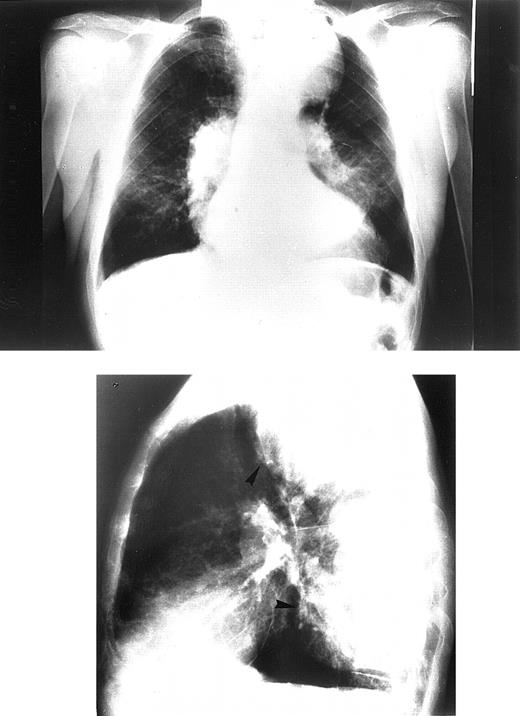

Chest radiographs revealed increased cardiothoracic index levels in 54 (49%) patients. Eighteen (16.3%) had prominent pulmonary arteries. Signs of obvious bone marrow expansion were present in 25 (22.7%) patients and included intrathoracic extramedullary hemopoietic masses in 21 (19%) patients and widening of ribs in 10 (9%) patients (Figure 1). Pericardial calcification was found in a 42-year-old patient with a history of pericarditis but no history of tuberculosis and negative findings on the Mantoux test (Figure 2).

Chest radiograph of the oldest patient with congestive heart failure.

Frontal view (upper panel). Lateral view (lower panel). Patient shows signs of pulmonary hypertension combined with large intrathoracic extramedullary hemopoietic masses.